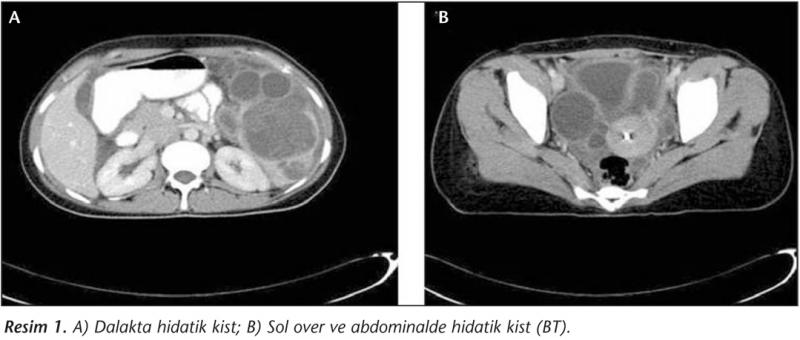

Hidatik kistlerin patlaması, anaflaktik şoka neden olabilecek ciddi bir durumdur. Bu nedenle, kistin varlığı veya semptomların ortaya çıkması durumunda tıbbi bir uzmana başvurulması önemlidir. Tanı Yöntemleri Hidatik kistin tanısı, klinik belirtilerin yanı sıra çeşitli görüntüleme yöntemleri ile konulabilir. Tanı yöntemleri şunlardır:

Bu yöntemler, kistin boyutunu, sayısını ve yerleşimini belirlemede yardımcı olur. Ayrıca, kistin içeriğinin değerlendirilmesi için gerektiğinde invaziv işlemler yapılabilir. Tedavi Yöntemleri Hidatik kistlerin tedavi yöntemleri, kistin boyutuna, yerleşimine ve hastanın genel sağlık durumuna bağlı olarak değişiklik göstermektedir. Tedavi yöntemleri şunlardır: